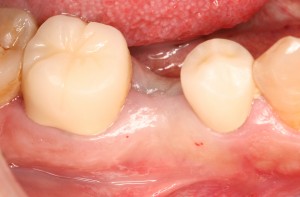

被せ物装着後